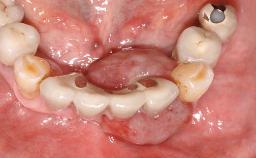

In 2004, the patient, a smoker, began dental treatment at the ACTA graduate clinic. She was a TV producer exposed to a lot of stress in her job and had a sick husband. Her maxillary teeth had been extracted, as had the mandibular canines, premolars, and molars, with the exception of tooth 34. She received a complete maxillary denture and a mandibular skeleton denture. In October 2007, her maxilla was augmented by an oral and maxillofacial surgeon; in March 2008, implants (Biomet 3i, Palm Beach, Florida, USA) were inserted at that same clinic. In 2008, the patient was presented at the Department of Oral Implantology and Prosthetic Dentistry to request restorations for her implants. An implant-supported overdenture was planned. She also asked if we could restore her occlusion with fixed prosthetics.